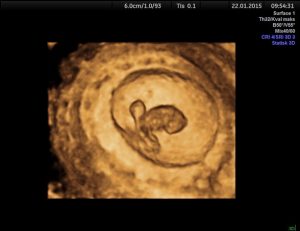

Ultralyd tidlig i svangerskapet

3D/4D-ultralyd

Early 3D ultrasound